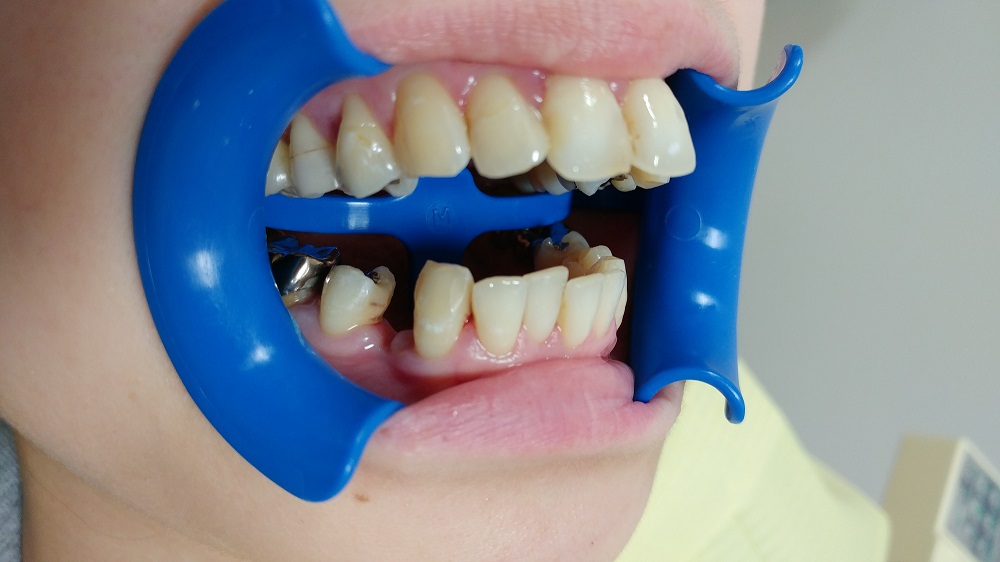

しかし、この処置は3つのパーツに分かれているためにその必要もない

そして、エナメル質を残しているので、万一の時にはやり直しがきく

他の治療に移る事も充分可能であるのだ全く持って素晴らしい治療方法ではないだろうか

兎も角も・・・ その技工所いわく県内初のヒューマンブリッジは

このようにしてセットされました